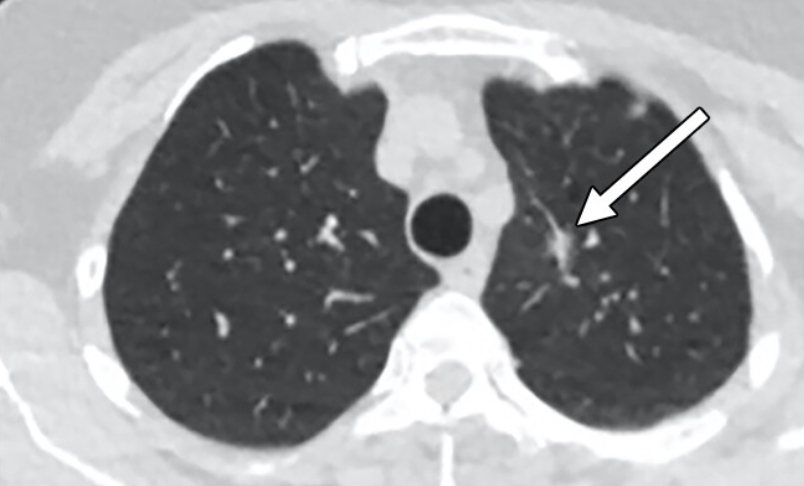

입안에 생기는 편평세포암은 하얀색이나 붉은색 반점, 혹은 작게 돋아오른 혹으로 나타납니다. 혀, 잇몸, 입천장 등에서 통증 없이도 변화가 생길 수 있어 구내염으로 착각하기 쉽습니다. 편평세포암종 초기 증상 폐나 기관지에 발생할 경우 기침이 오래 지속되고 피 섞인 가래가 나오기도 합니다. 호흡이 짧아지고, 목소리가 변하거나 가슴이 답답한 느낌이 들면 감기라고 생각하지 말고 진료를 받아야 합니다.

폐 편평세포암은 폐암의 한 유형으로, 주로 흡연과 관련이 있습니다. 기침이 3주 이상 지속되거나 피 섞인 가래, 숨이 차는 증상이 있으면 검사를 받아야 합니다. 흡연자는 비흡연자보다 편평세포암 발생 위험이 몇 배나 높습니다. 금연은 가장 강력한 예방책이며, 폐 건강을 지키는 가장 직접적인 방법입니다.

진단은 흉부 X선, CT, 기관지 내시경, 조직검사로 이뤄집니다. 치료는 수술, 방사선, 항암치료, 면역치료가 병합됩니다. 최근에는 맞춤형 치료제가 도입되어 생존율이 향상되고 있습니다.